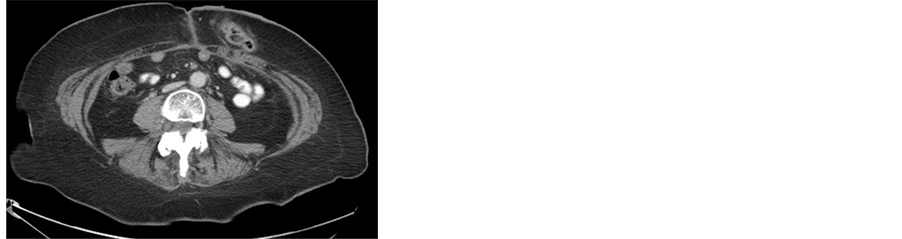

(a)(b)(c)(d)

Figure 5. (a) Incarcerated hernia; (b)-(d) CT scan of the abdomen shows metastases in the subcutaneous tissue in the sites of the laparoscopic ports.